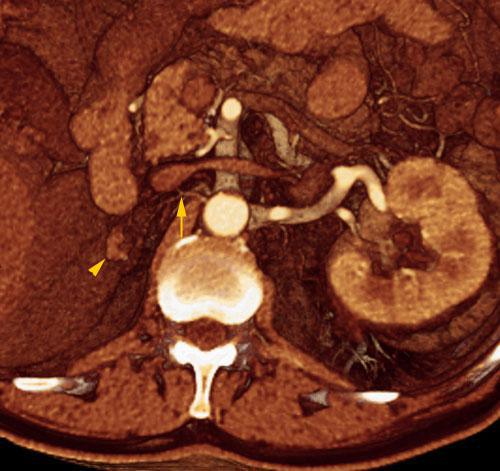

Hipoplasia renal 1

VR seccional. Visión axial caudal. Riñón derecho (punta de flecha) de muy pequeño tamaño en fosa renal. Obsérvese la presencia de los vasos renales (flecha) también de aspecto hipoplásico